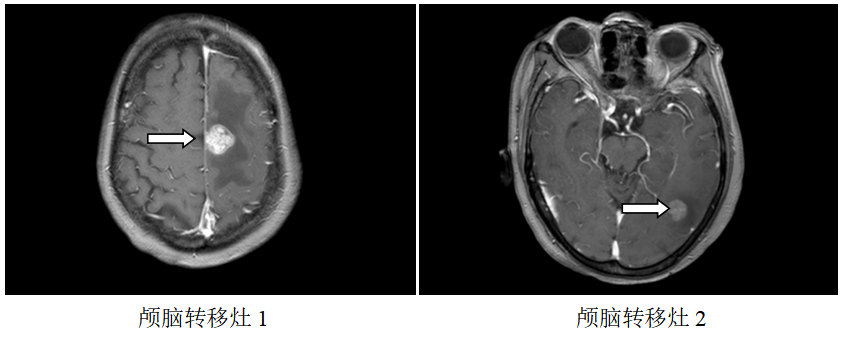

颅脑MR:左侧额、枕叶脑转移瘤;

局部放疗:2019.7.23~2019.8.7予脑转移灶调强放疗DT3900CGy/13F。

再次放疗:2020.06.04复查颅脑MR:原左侧额、枕叶脑转移瘤较前缩小,右侧颞叶新增转移瘤,于2020.6.15-6.26予脑转移灶调强放疗DT3000CGy/10F。

继续维持治疗:新增右侧颞叶脑转移灶,配合脑转移局部放疗,其余病灶好转,继续原方案全身治疗。

该例患者为胃癌脑转移。脑转移患者的抗HER2治疗一直存在着大分子单抗和小分子TKI之争。有研究显示,由于脑肿瘤部位的血脑屏障受损,通透性要高于正常脑组织,因此曲妥珠单抗可以透过血脑屏障到达病灶部位,尤其是一些接受过脑放疗的病人更是如此。对这例患者,初诊时即存在脑转移,选择了曲妥珠单抗+化疗作为一线治疗,配合脑部放疗,达到PR效果,而后新增脑转移灶,再次放疗,继续曲妥珠单抗治疗,仍达到PR效果,患者前期予赫赛汀,后期因经济原因改予汉曲优,肿瘤依然进一步控制,患者OS>28个月。

本例报道为HER2阳性胃癌患者,初诊时已经出现脑转移。由于曲妥珠单抗是一个大分子单克隆抗体,其通过血脑屏障的能力有限,但一些学者认为如果发生肿瘤脑转移,脑肿瘤部位的血脑屏障受损,通透性要高于正常脑组织,因此曲妥珠单抗可以透过血脑屏障到达病灶部位,尤其是接受过脑放疗的患者。因此对于HER2阳性胃癌脑转移患者,推荐使用含曲妥珠单抗的抗HER2治疗方案,本例患者初诊即存在脑转移,选择了曲妥珠单抗+FOLFOX作为一线治疗,配合脑部放疗,达到PR效果后采用卡培他滨+曲妥珠单抗维持治疗,停药3个月新增脑转移灶,再次放疗,继续选用曲妥珠单抗联合卡培他滨治疗,仍达到PR效果,获得了较好的疗效。